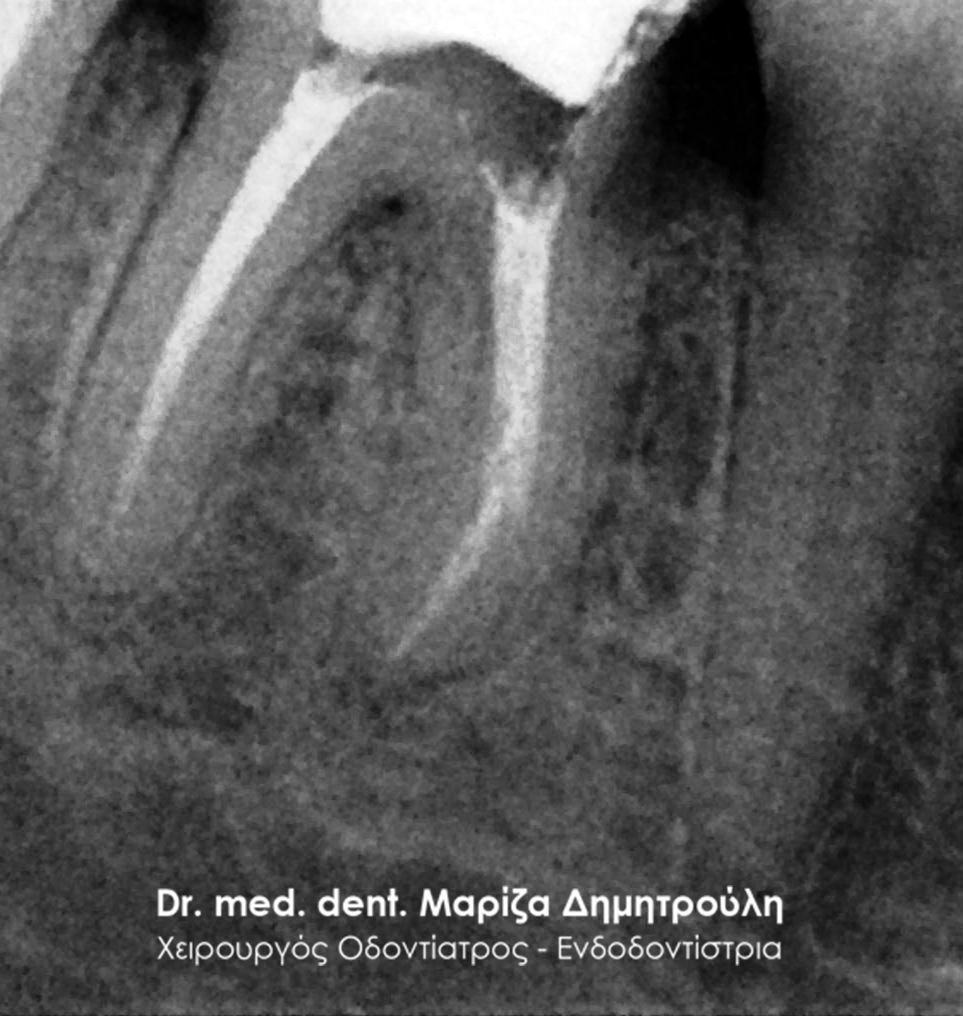

Root canal retreatment

BEFORE

The metallic stift after removing it from the tooth